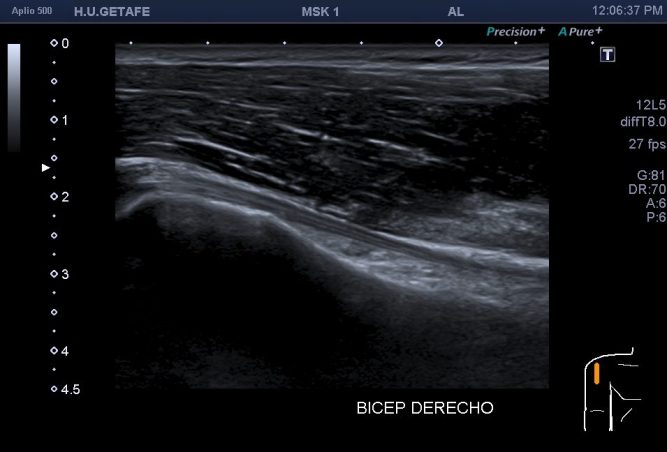

Llevo tiempo intentando subir este breve post. Tiene que ver con un artefacto ya muy explicado por aquí, la Anisotropía, típico de la Eco MSK. En este caso en una proyección muy típica que podemos ver de modo habitual en l exploración del tendón del Bíceps, en el estudio de protocolo del Hombro en el corte en eje largo.

En la imagen 1 ves un tendón del Bíceps en eje largo, de aspecto hipoecogénico, parece anisotrópico. En la imagen 2 ves una tendón de aspecto normal, es el mismo paciente en el mismo momento.